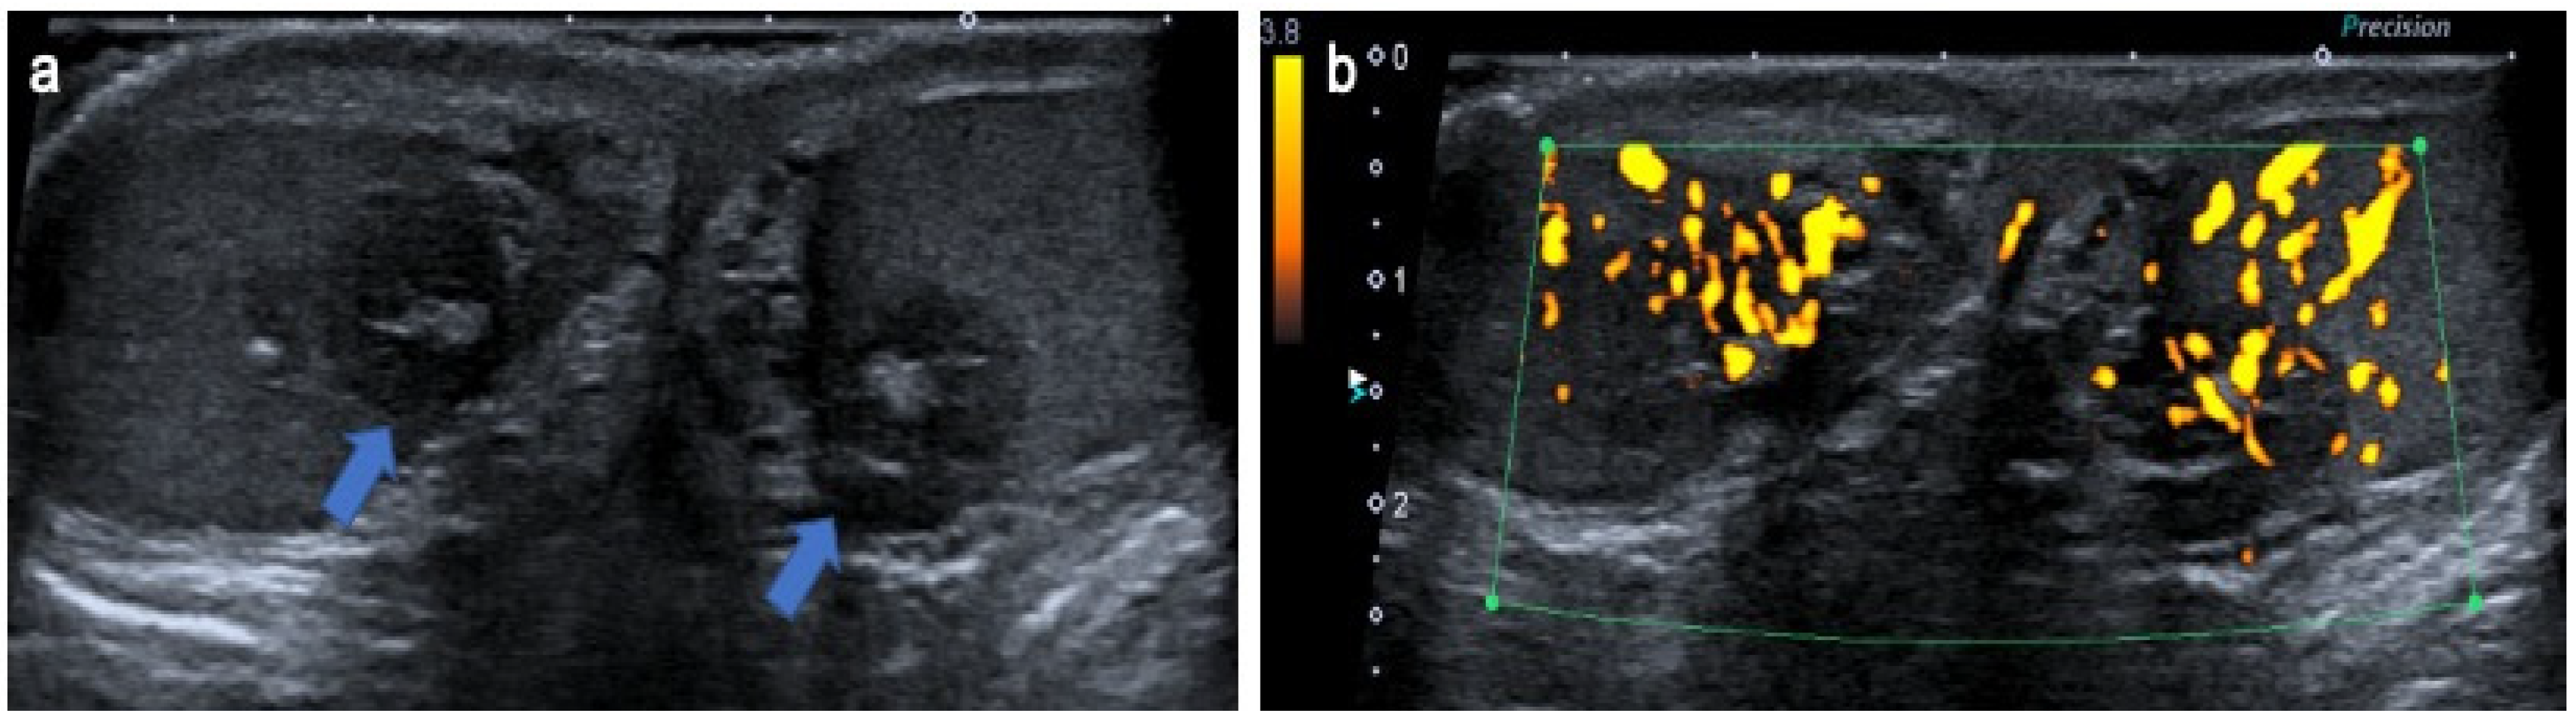

4.6. Lymphoma and Leukemia

- Mazzu, D.; Jeffrey, R.B.; Ralls, P.W. Lymphoma and leukemia involving the testicles: Findings on gray-scale and color Doppler sonography. Am. J. Roentgenol. 1995, 164, 645–647. [Google Scholar] [CrossRef]

- Bertolotto, M.; Derchi, L.E.; Secil, M.; Dogra, V.; Sidhu, P.; Clements, R.; Freeman, S.; Grenier, N.; Mannelli, L.; Ramchandani, P.; et al. Grayscale and Color Doppler Features of Testicular Lymphoma. J. Ultrasound Med. 2015, 34, 1139–1145. [Google Scholar] [CrossRef]